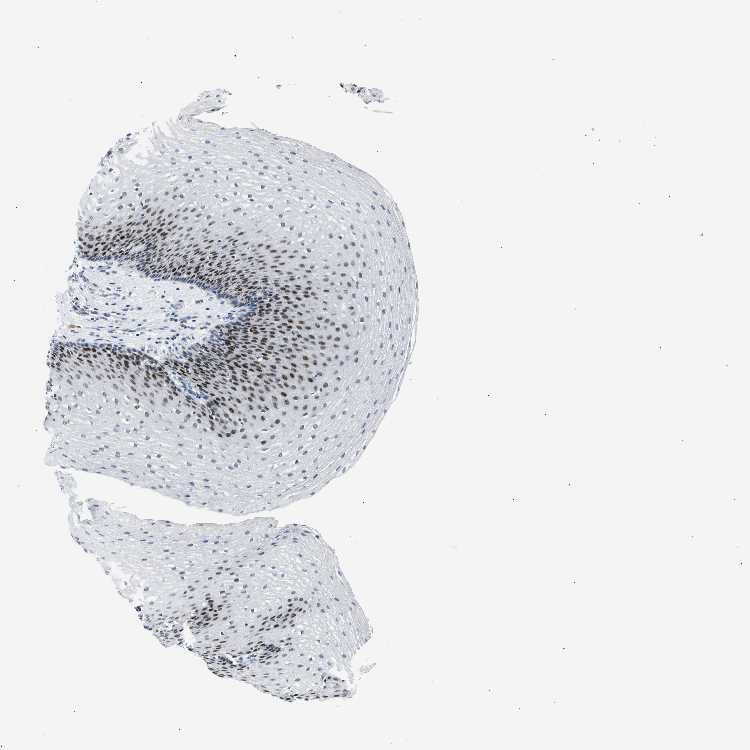

ESOPHAGUS - Antibody stainingi

Antibody staining in the annotated cell types in the current human tissue is reported as not detected, low, medium, or high, based on conventional immunohistochemistry profiling in selected tissues. This score is based on the combination of the staining intensity and fraction of stained cells.

Each image is clickable and will lead to virtual microscopy that enables deeper exploration of all samples and also displays staining intensity scores, fraction scores and subcellular localization as well as patient and tissue information for each sample.

Antibody HPA024352Antibody HPA026853Antibody CAB011576Antibody CAB016336

Squamous epithelial cells HighHighHighHigh